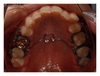

Two main systems are used to retract the anterior teeth: miniscrews (Figures 1 and 2) [36–44] and miniplates [45, 46].

Most of the published studies on the retraction of anterior teeth with miniscrews are case reports [29, 41–44] (Figure 1(a)). In the cases presented, the miniscrews were applied directly to the hooks on the archwire to retract all upper 6 anterior teeth simultaneously with a loading force of about 150 g. Furthermore, the extraction space was fully utilized in the retraction of anterior teeth without anchorage loss. The posterior teeth even moved distally slightly in some cases [41–44]. One of the advantages of the mechanics involved in these cases was the direct application of load to the vertical hooks on the archwire: in this setup, the point of force application was close to the center of resistance of the anterior segment, thereby allowing bodily sliding of the whole segment with minimal tipping, and in turn, shortening the treatment time [44] (Figure 1(b)).

In the cases inserted within palatal, Wehrbein et al. [24] prospectively studied 9 patients with Class II malocclusion in whom anchorage was indirectly reinforced by connection of a transpalatal bar to a palatal implant after extraction of the upper first premolars. The loading force applied was 200 g over 11 months, and the reduction of overjet ranged from 5.1 to 7.8 mm (mean, 6.22 mm). The loss of anchorage ranged from 0.2 to 1.6 mm, and was attributed to the deformation of the transpalatal bar (Figure 1(c)).